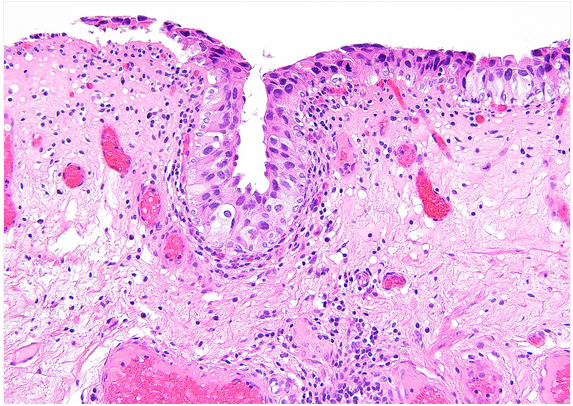

Penioe lesion

Dx:

Histo features

Penile linear schlerosis -> precursor to Lichen sclerosis/

Moderate lymphcytic infiltrate in LP.